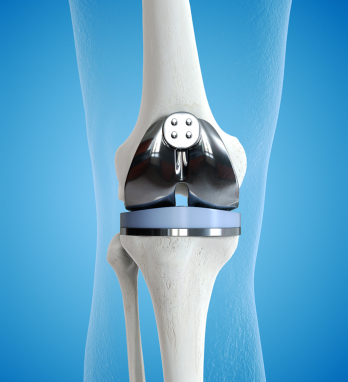

With state-of-the-art robotic joint replacement surgery offering greater accuracy, smaller incisions, and faster recovery times.

Trust DR. KUNAL PATEL and his expert teams for a successful joint replacement surgery, giving you a new lease on life.

The Benefits of Robotic Knee Replacement Surgery

In recent years, medical technology advancements have brought about a revolution in the field of orthopedic surgery, particularly in the realm of knee replacements.

The Impact of Robotics on Knee Replacement: Revolutionizing Orthopedic Surgery

In recent years, orthopedic surgery has undergone a revolutionary transformation through the integration of robotics in knee replacement procedures.

Knee Replacement Surgery: A Comparison of Traditional and Robotic Techniques

When it comes to addressing debilitating knee pain and restoring mobility, knee replacement surgery has been a transformative solution for many individuals.

Chennai Apollo hospital performs 370 robot-assisted orthopedic procedures in 10 months

A robotic knee replacement is just like a traditional knee replacement. The surgeon removes damaged tissue and replaces it with an artificial joint.